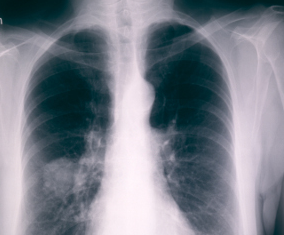

肺癌是美国男性和女性癌症相关死亡的主要原因,尤其是男性,而女性近年来肺癌相关死亡也逐年增加。根据NCI统计数据,约22.12万美国人被诊断为肺癌,今年预计有15.8040万人将死于